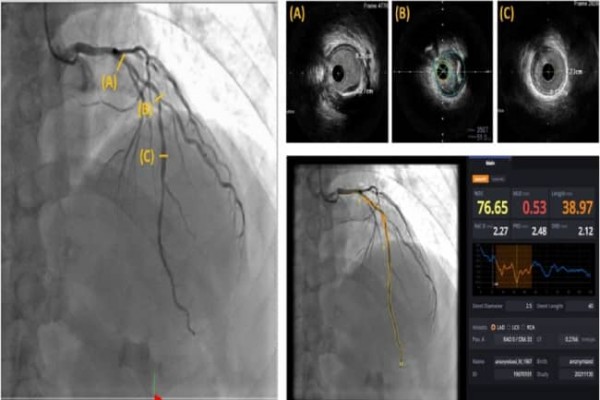

사진1. 심혈관 조영술 영상(좌), 혈관 내 초음파(우-상), AI(우-하), 심혈관 조영술 영상을 바탕으로 AI가 각 부위(A~C) 병변의 길이 등을 분석해서 표시하고 있다.

이에 강시혁 교수팀은 심혈관을 자동으로 분석해주는 인공지능 소프트웨어(AI-QCA)가 혈관 내 초음파를 대체할 수 있는지 알아보기 위해 혈관 내 초음파를 추가로 시행한 환자 47명을 대상으로 ▲협착된 직경 백분율 ▲ 협착된 영역 백분율 ▲병변 길이 ▲ 최소 내강면적 등의 결과가 인공지능 소프트웨어 결과와 얼마나 일치하는지 확인했다.

그 결과 시술시 중요한 지표인 혈관의 직경 및 넓이, 병변의 길이가 혈관 내 초음파 검사로 측정한 지표와 인공지능 소프트웨어로 측정한 지표가 최소 60%에서 최대 80%까지 상관성을 보이는 것으로 나타났다. 또한, 병변 식별률은 88.7%, 병변 크기의 차이는 10mm 내외로 큰 차이가 없었다.

특히, AI 소프트웨어는 실시간으로 심혈관의 병변여부, 병변의 길이, 직경 등의 정보를 제공하여 스텐트의 길이와 직경을 결정하는데 도움을 줄 수 있어 의사의 높은 숙련도를 요구하는 스텐트 시술에 인공지능 소프트웨어를 병행해서 사용한다면 더욱 효과적인 검사 및 시술을 할 수 있을 것으로 보인다.